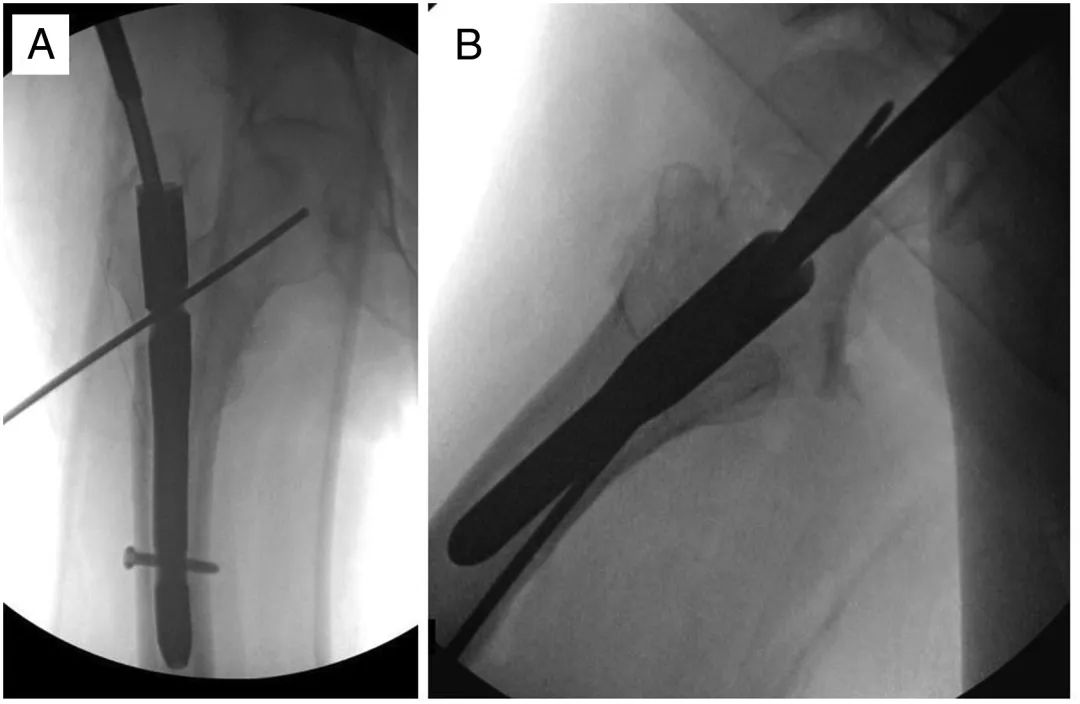

Затем в субхондральную кость головки бедренной кости по оси шейки бедренной кости вводят новый винт или спиральную лопасть, следя за тем, чтобы не проникнуть в головку (рис. 4).Винт намеренно вводят, избегая прохода предыдущего стержня, но по-прежнему направляя его конец к центру головки бедренной кости.(Рисунок 5)

Рисунок 4. Переднезаднее (А) и боковое (В) изображение другого пациента, показывающее введение иглы для прокалывания вдоль пути нового гвоздя.